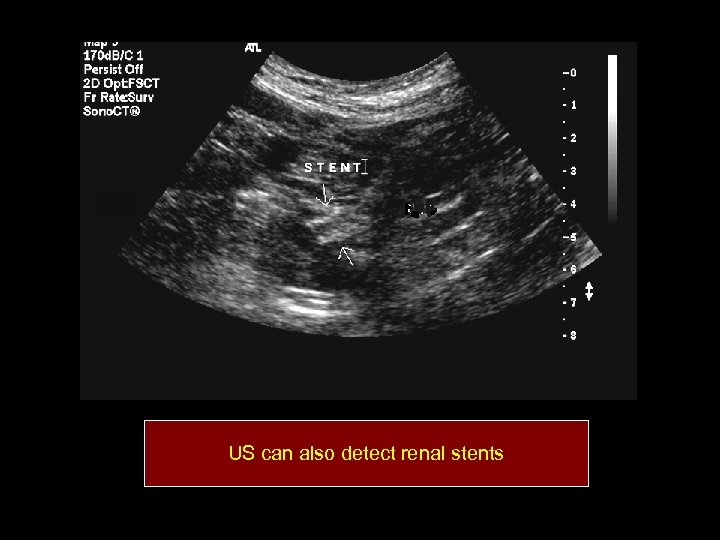

US can also detect renal stents